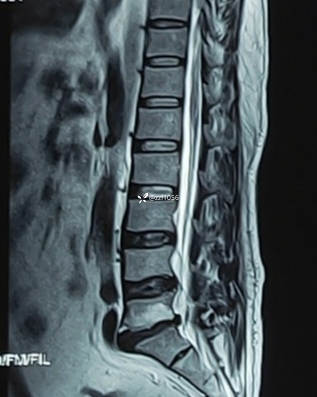

症像不符的一例腰椎间盘突出症,是否考虑极外侧突出,减压融合后效果良好

【临床诊断】:腰椎间盘突出症 终板炎

影像上可看到L5/S1间隙非常狭窄,退变严重,两侧均有神经根激惹,椎间孔狭窄,L5下终板终板炎较重,左下肢无任何症状,右下肢L5S1根症状均存在,建议椎间孔镜下减压L5根和S1根,患者拒绝,因咨询多家医院要求开放融合。